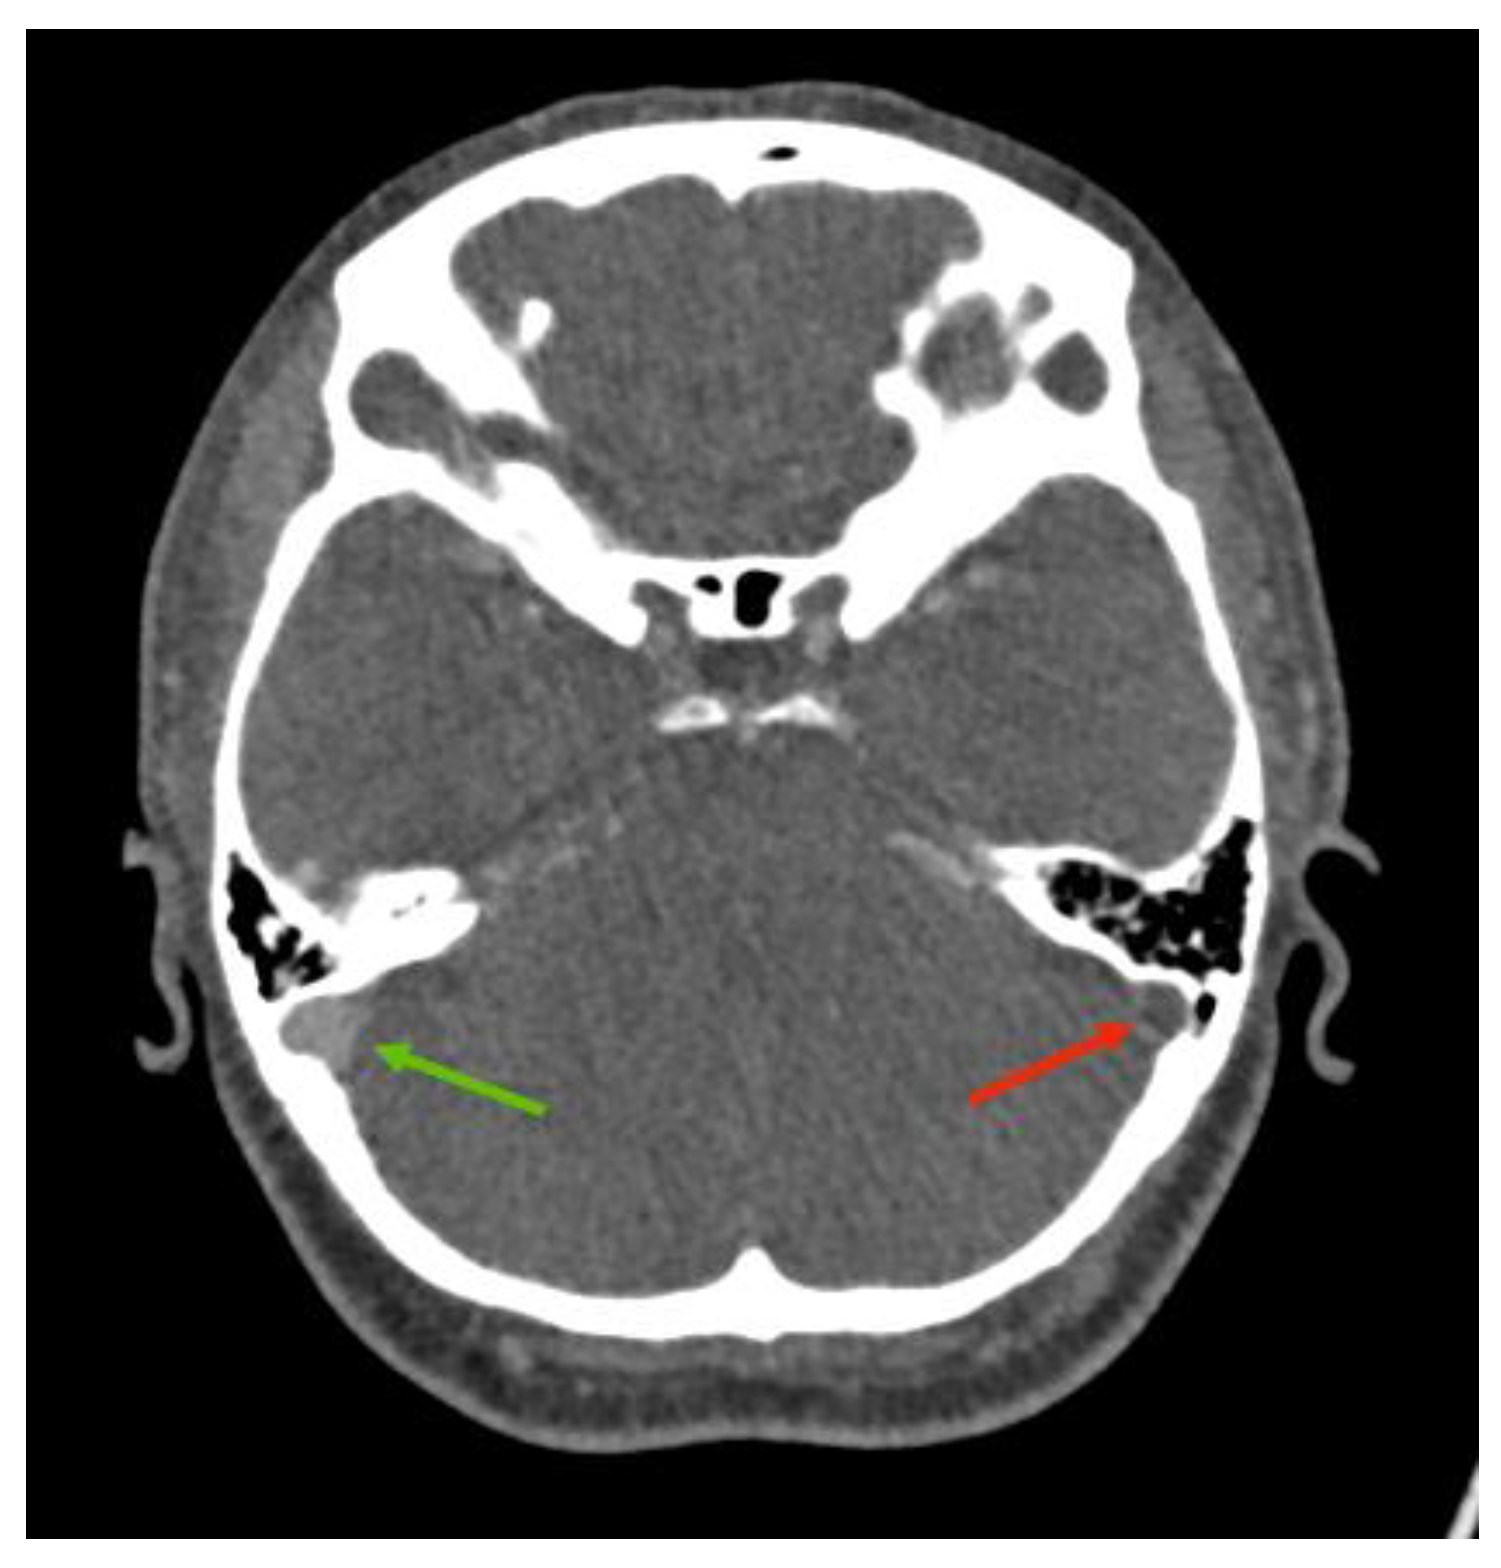

3.2. Imaging Role